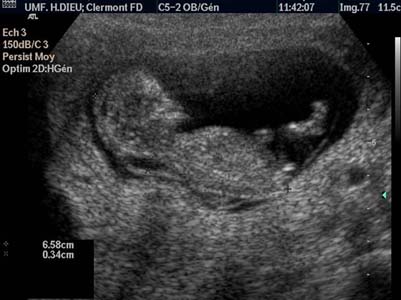

Epaississement de la nuque